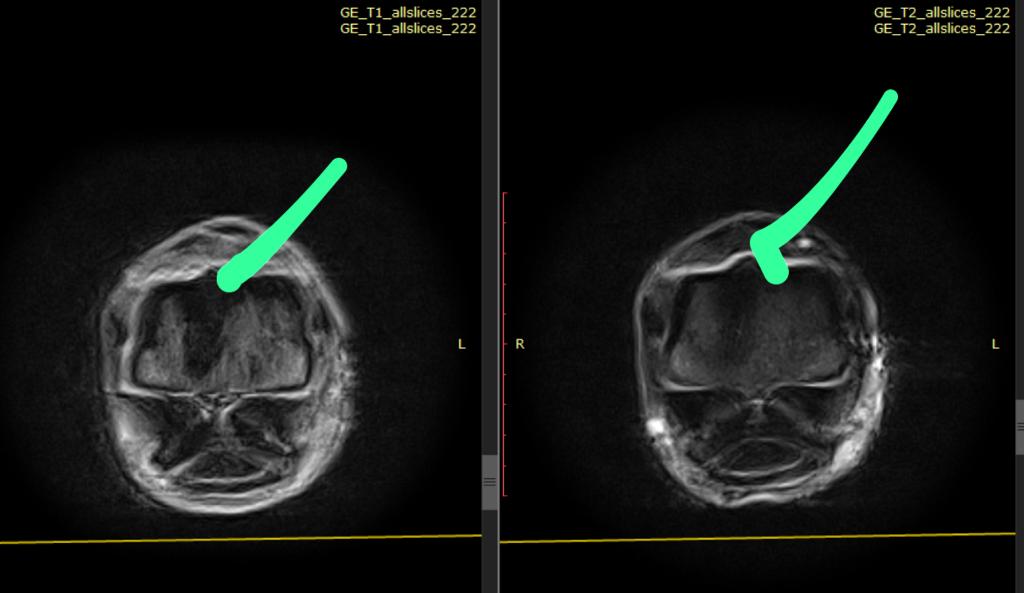

У пациента хроническая хромота на правую грудную конечность продолжалась больше двух лет. Рабочие паузы даже в несколько месяцев не давали полного восстановления.

По результатам диагностической анестезии была определена область путового сустава, но ни рентгенологическое, ни ультразвуковое обследование не позволяло установить диагноз.

В результате МРТ-диагностики было установлено повреждение по месту прикрепления латеральной ножки межкостного мускула к проксимальной сезамовидной кости, что коррелировало с отмеченной ранее на рентгене небольшой костной реакцией по краю сезамовидной кости.

После постановки диагноза можно более точно определить сроки восстановления, которые также могут быть подтверждены по повторным результатам МРТ.